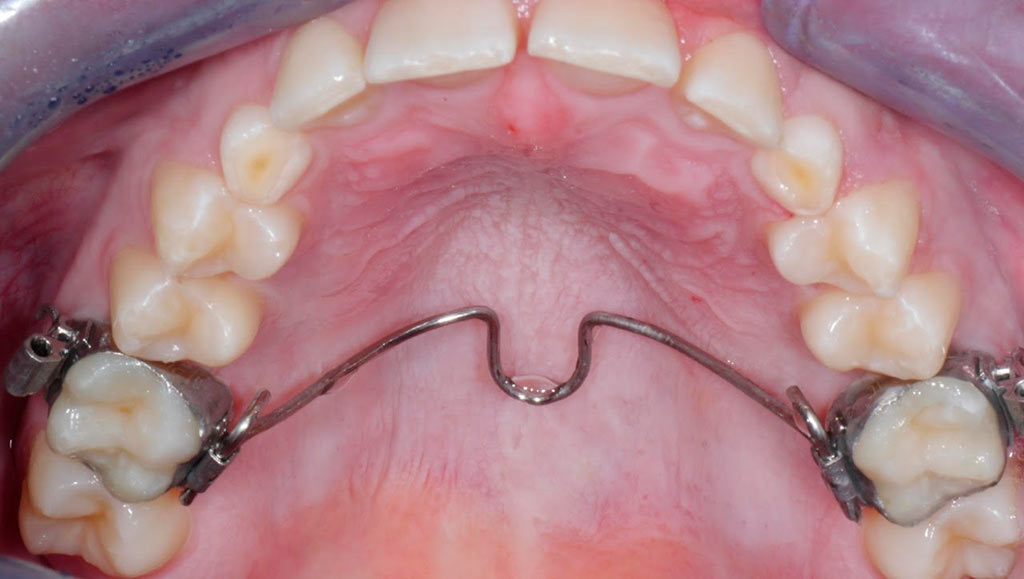

Tracción de canino con k9